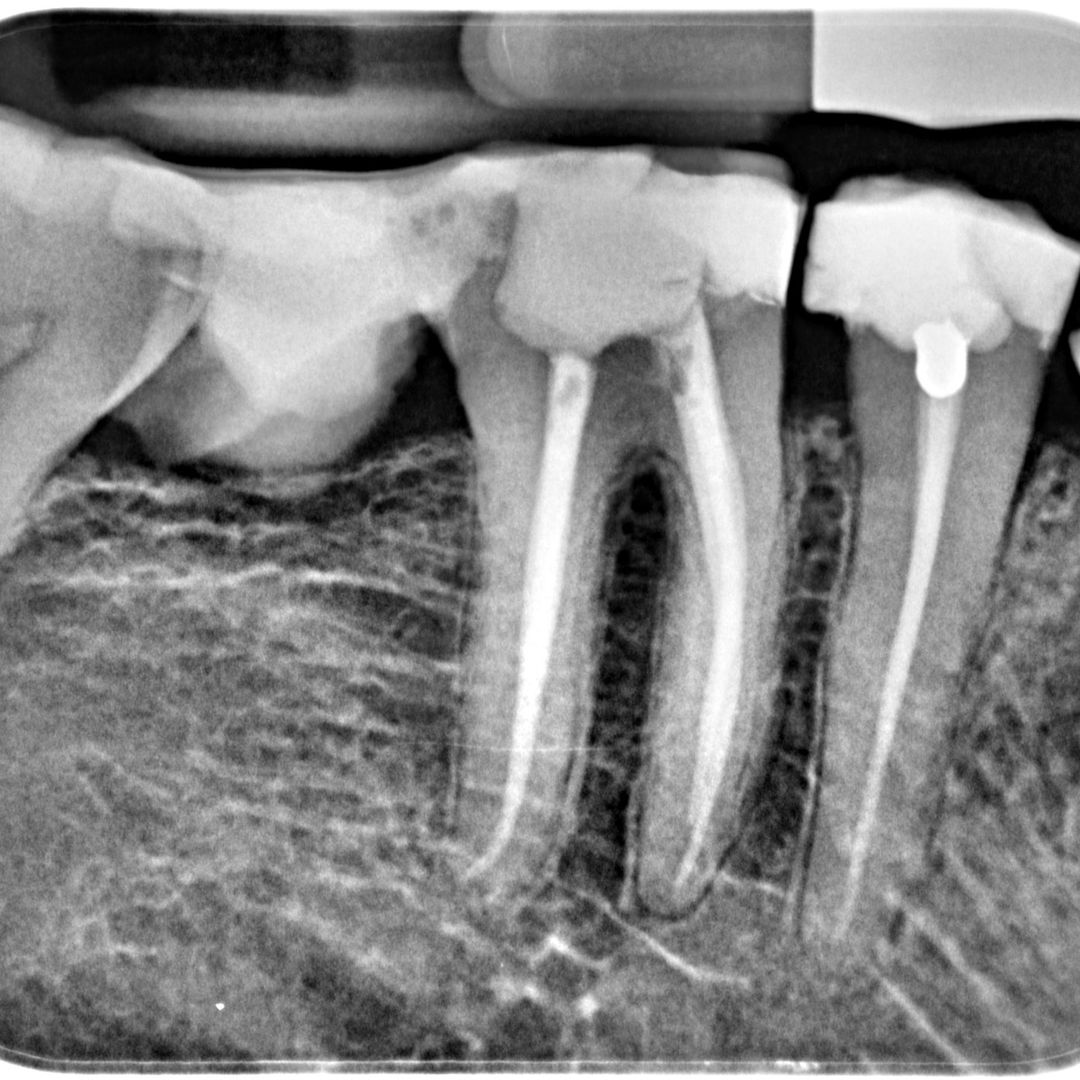

Root Canal Treatment

Root Canal Treatment is a procedure performed on the infected tooth to remove the decay affecting the pulp (underlying tissue containing blood vessels and nerve supply to a tooth). Simple filling procedure cannot restore a tooth’s dental health when the infection has encroached the pulp. Root canal therapy is the only alternative to save such tooth from being extracted. The main objective of root canal treatment is to preserve the infected existing natural tooth by disinfection. During a root canal therapy, access to the root canal present inside the root of a tooth is gained and the infected tissue is removed entirely. Hence Root Canal treatment bypasses extraction of the infected tooth and its replacement procedures thereby saving time and money.